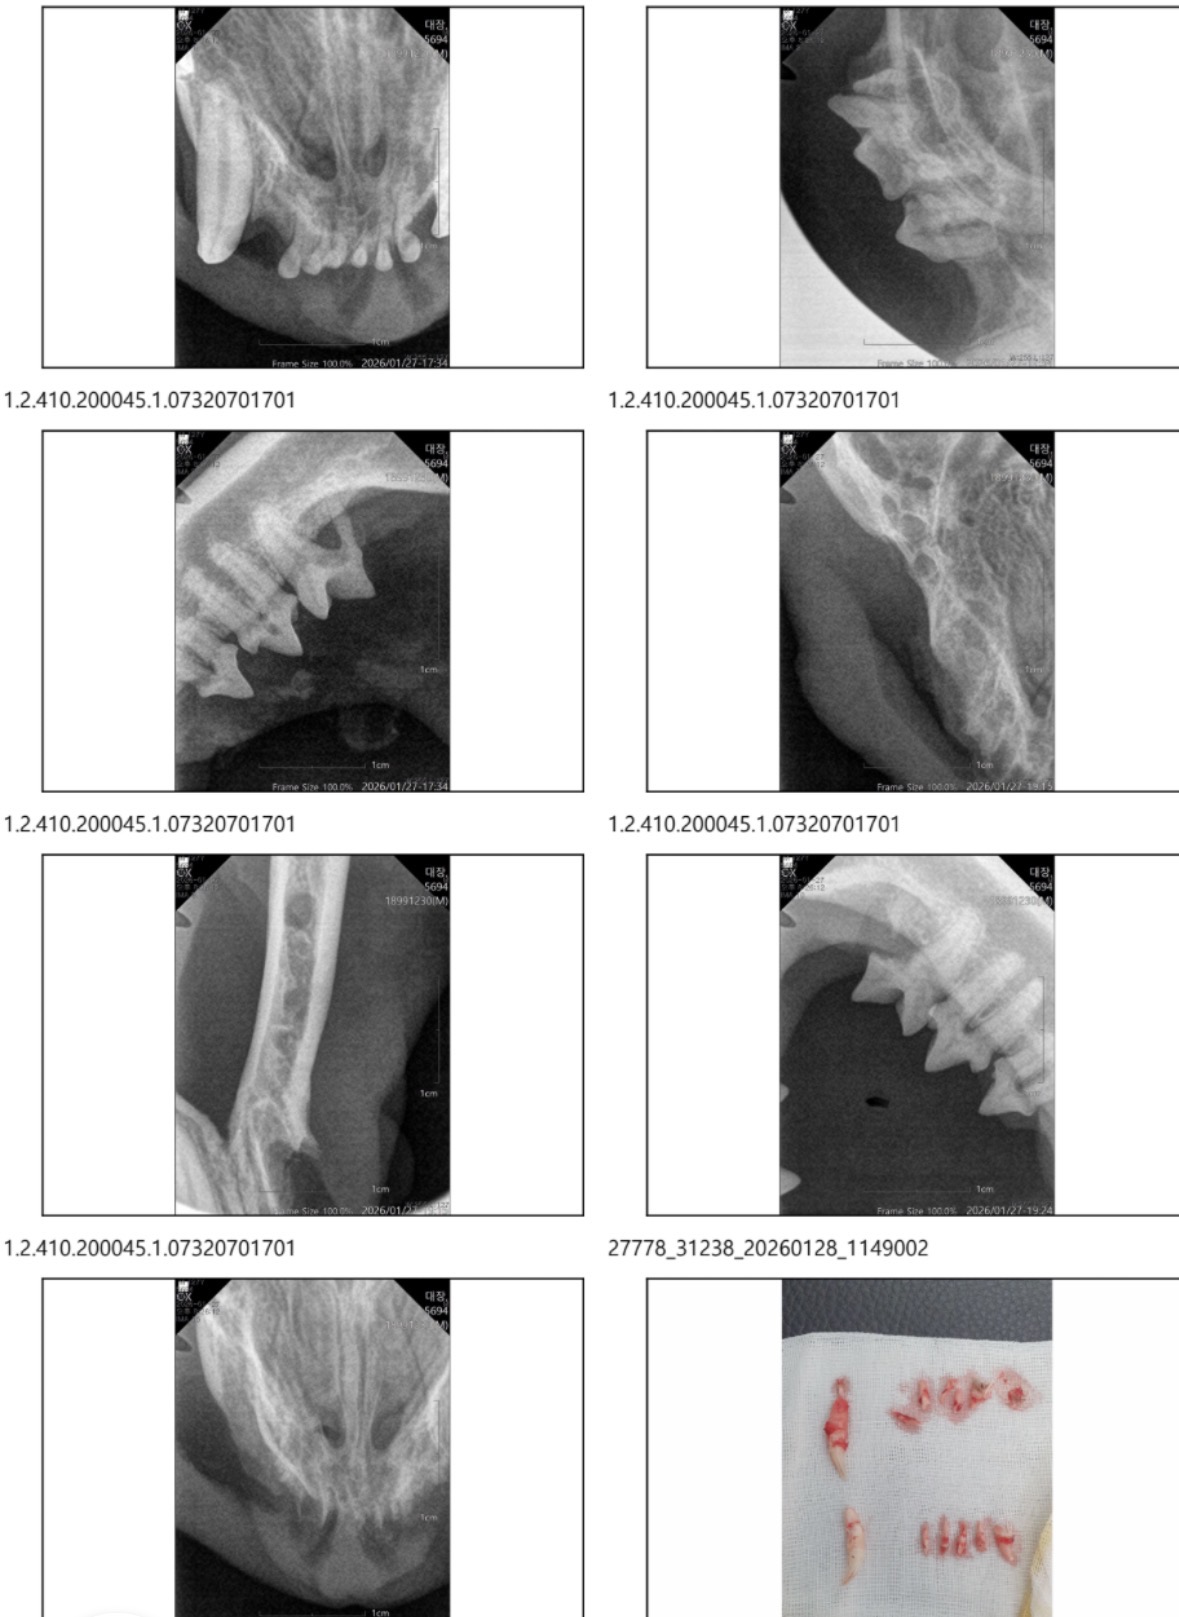

| 대상묘 병명 | 구내염 |

| 치료과정 | 26.01.27 제가 소유한 통덫으로 대장이를 밥놓는자리에서 구조했습니다. 치료를 위해서는 전날 금식이 좋다고했지만 전날저녁을 소량 먹은상태여서 마취를 한 상태기에 혹시나 하는 상황에 대비해 오전에 병원에 방문하였지만 저녁 수술로 진행됨을 먼저 고지받았습니다. 땡큐독병원이 치과 전문 동물병원이여서 이곳에서 진행하게 되었습니다 이전에 제가 돌보던 길냥이들을 잘 돌봐주신곳이기도하고 길냥이들 할인도 해주시는 고마운 곳입니다:) 이전에 허피스 약 처방받으러 갔을때 사진을 미리 보여줬던 터라 의사선생님께서 알아보셨고, 치료후 연락을 주신다하셨습니다 병원 마감시간이 한참 지난시간이여도 연락이오지않아서 다음날로 수술이 미뤄지는건지 걱정했는데 그때 전화가 왔습니다 구내염으로 인한 상태가 맞았으며, 전발치 진행했다고 하셨습니다 잇몸이 많이 부어있는 상태고 시간이 좀 지난상태로 지낸거같아보인다. 많이 아팠을 거란 말을 하셨어요ㅠㅠ 전발치를 진행할경우 저는 고양이가 잘 못먹는거아닌가 하는 고민을 가장많이했었는데 오히려 먹는건 훨씬 잘 먹으며, 다만걱정인건 길냥이기 때문에 서열에 밀려나 밥자리로 안올수 있단 말씀이셨습니다. 제가 두는 밥자리에 오지않더라도 치료를 하면 다른곳에서라도 먹을순 있겠지 라는 생각으로 (지금은 아예 먹지를 못하니) 치료를 진행한 것이였고 일단 병원에 5-7일간 입원해보며 경과를 봐야한다하셨습니다. 잘먹으면 금방 퇴원가능하단 희망적인 말씀도 듣게되었습니다 ㅎㅎ |

| 대상묘 치료중 사진 | ![]() ![]() ![]() ![]() ![]() ![]() |